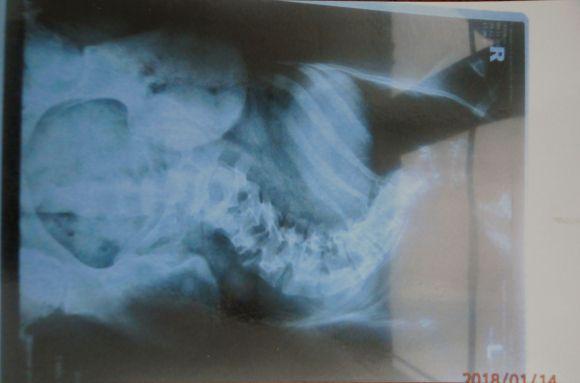

Лізі Насталенко 12 років, шість з них вона вимушена практично цілодобово носити спеціальний корсет. У неї сколіоз 4 ступеню. Якщо їй зараз не зробити операцію на хребті, вона може померти.

– У Лізи хребет не просто викривлений, він ще й прокручений по своїй осі, – розповідає батько Юрій Насталенко. – Лікарі нам казали, що треба буде робити операцію, але не раніше 15 років. Коли дитина перестає інтенсивно рости. Та хвороба почала дуже швидко прогресувати і ми більше не можемо чекати.